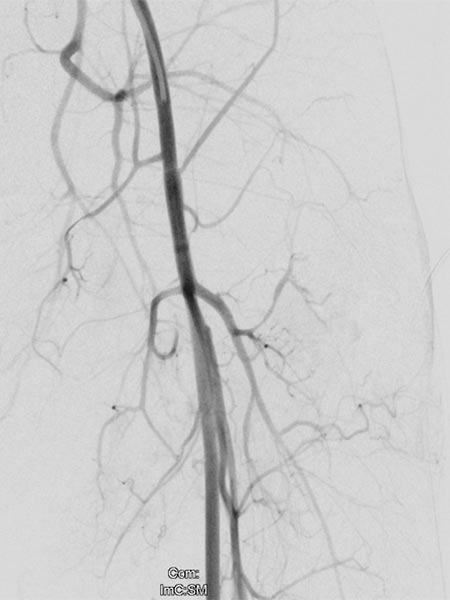

As there was still no tendency to regression of the tumor at the end of the 3rd year, embolization was performed after biopsy to induce involution. Digital subtraction angiography (DSA) shows a microcatheter superselectively introduced into a tumor vessel. The tumor is heavily perfused and lobulated, very early venous outflow, typical of an NICH.

Particle embolization with spherical particles 250 micrometers in size via the microcatheter inserted superselectively into the tumor.

More tumor vessels with blush-like diffuse enhancement, typical of a vascular tumor / NICH. All these vessels must be selectively embolized to induce involution.

Further selective particle embolization. The embolization particles mixed with contrast medium remain in the tumor vessels.

Overview angiography via the left external iliac artery also shows no remaining perfusion of the tumor anymore, thus the tumor vascularization is successfully and superselectively completely occluded. All non-pathological arteries are preserved.